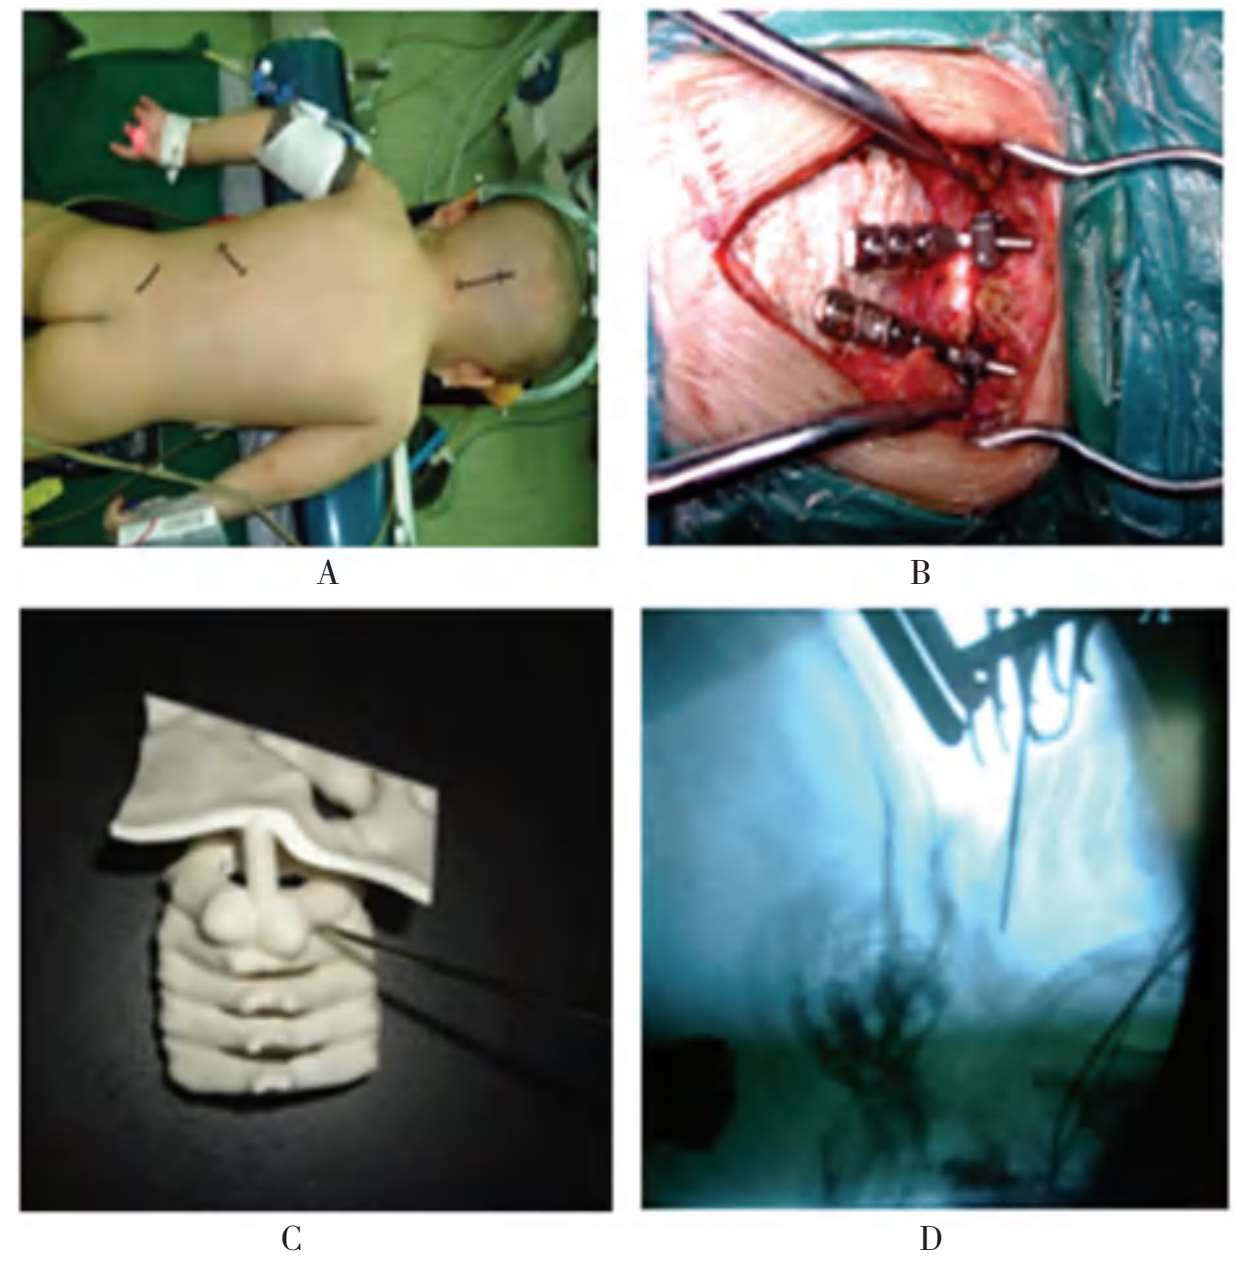

手术取俯卧位,头部放置在可调式头架上,维持牵引重量2kg。手术取枕颈部后正中切口,起自枕外隆突,止于C 3 棘突。切开皮肤、皮下组织,双极电凝止血(图1-29)。然后用电刀顺棘突两侧剥离椎旁肌肉。向上显露枕骨后方及寰枢椎后方结构,向下显露C 3 后方椎板及两侧的小关节。根据枢椎后方的解剖标志,确定螺钉进钉点,置入枢椎椎弓根螺钉及枢椎椎板螺钉各一枚。牵引下调整颈椎位置,尽可能让寰枢椎接近复位状态。选择两枚枕骨板,行C 2 与枕骨间的固定。透视下观察,复位满意后,将所有螺母拧紧。然后在髂后上棘取髂骨,用高速磨钻对枕骨后方及寰枢椎后方的皮质骨打磨后,进行植骨。最后放置负压引流,逐层关闭切口。

A~D.患儿接受后路寰枢椎复位,枕颈椎固定融合手术

图1-29 典型病例介绍